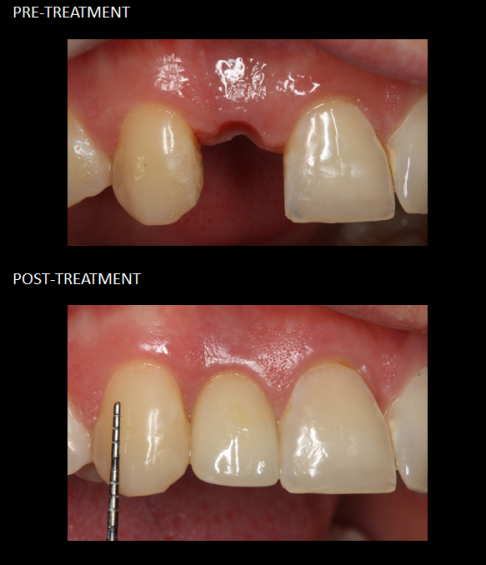

Restoration of front teeth with a crown (red), implant (yellow), and veneer (blue).